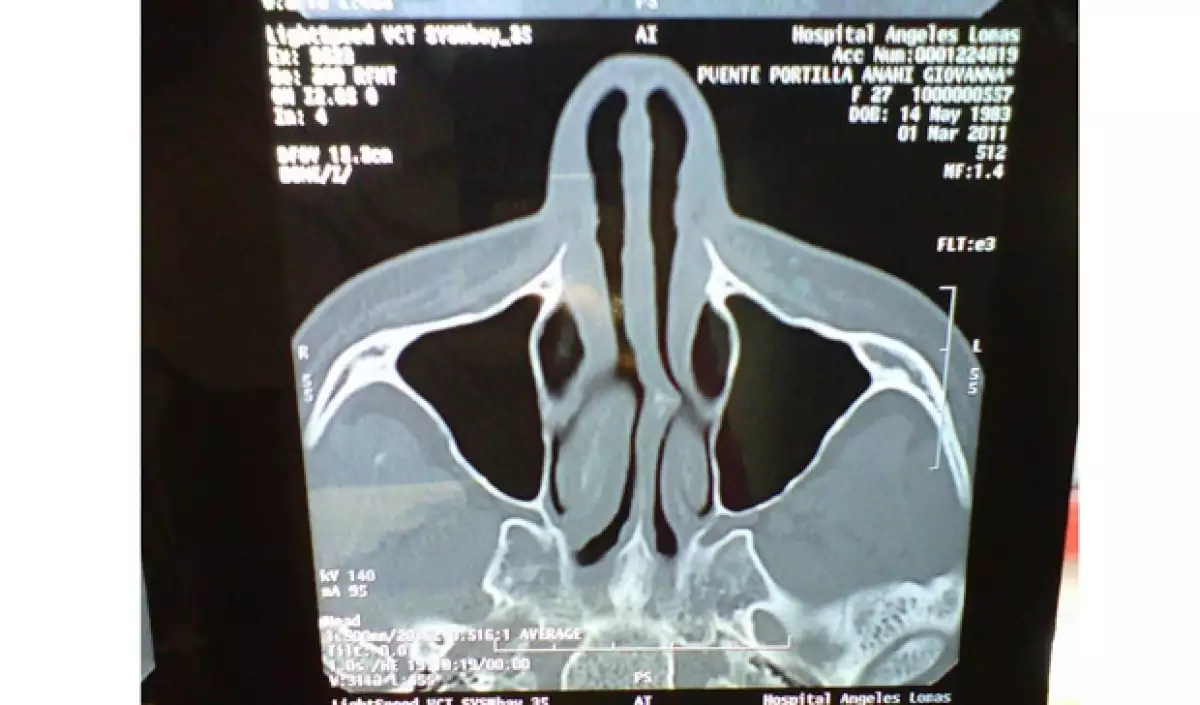

"Hace un par de días, se realizaron unos estudios médicos en los que a través de una tomografía se descubrió que el oxigeno que naturalmente debe de llegar al cerebro, estaba bloqueado en un gran porcentaje debido a un tabique desviado en la nariz causado por un golpe a temprana edad.

Por supuesto, durante el paso de las horas y los días, la intérprete de "Alérgico" se mostró un poco molesta por la prensa amarillista, así como por las personas que la atacaron inventando varias cosas de su entrada al hospital, por lo que subió la tomografía que le realizaron para desmentir todo lo que se había dicho de ella.

"Una vez más la tomografía de mi nariz... eso era lo q tenía" y remató escribiendo: "Ese fue un regalito para los malvibrosos q seguro ni le entienden pero eeequiiisquetevalga! Sean felices mundo" (sic).